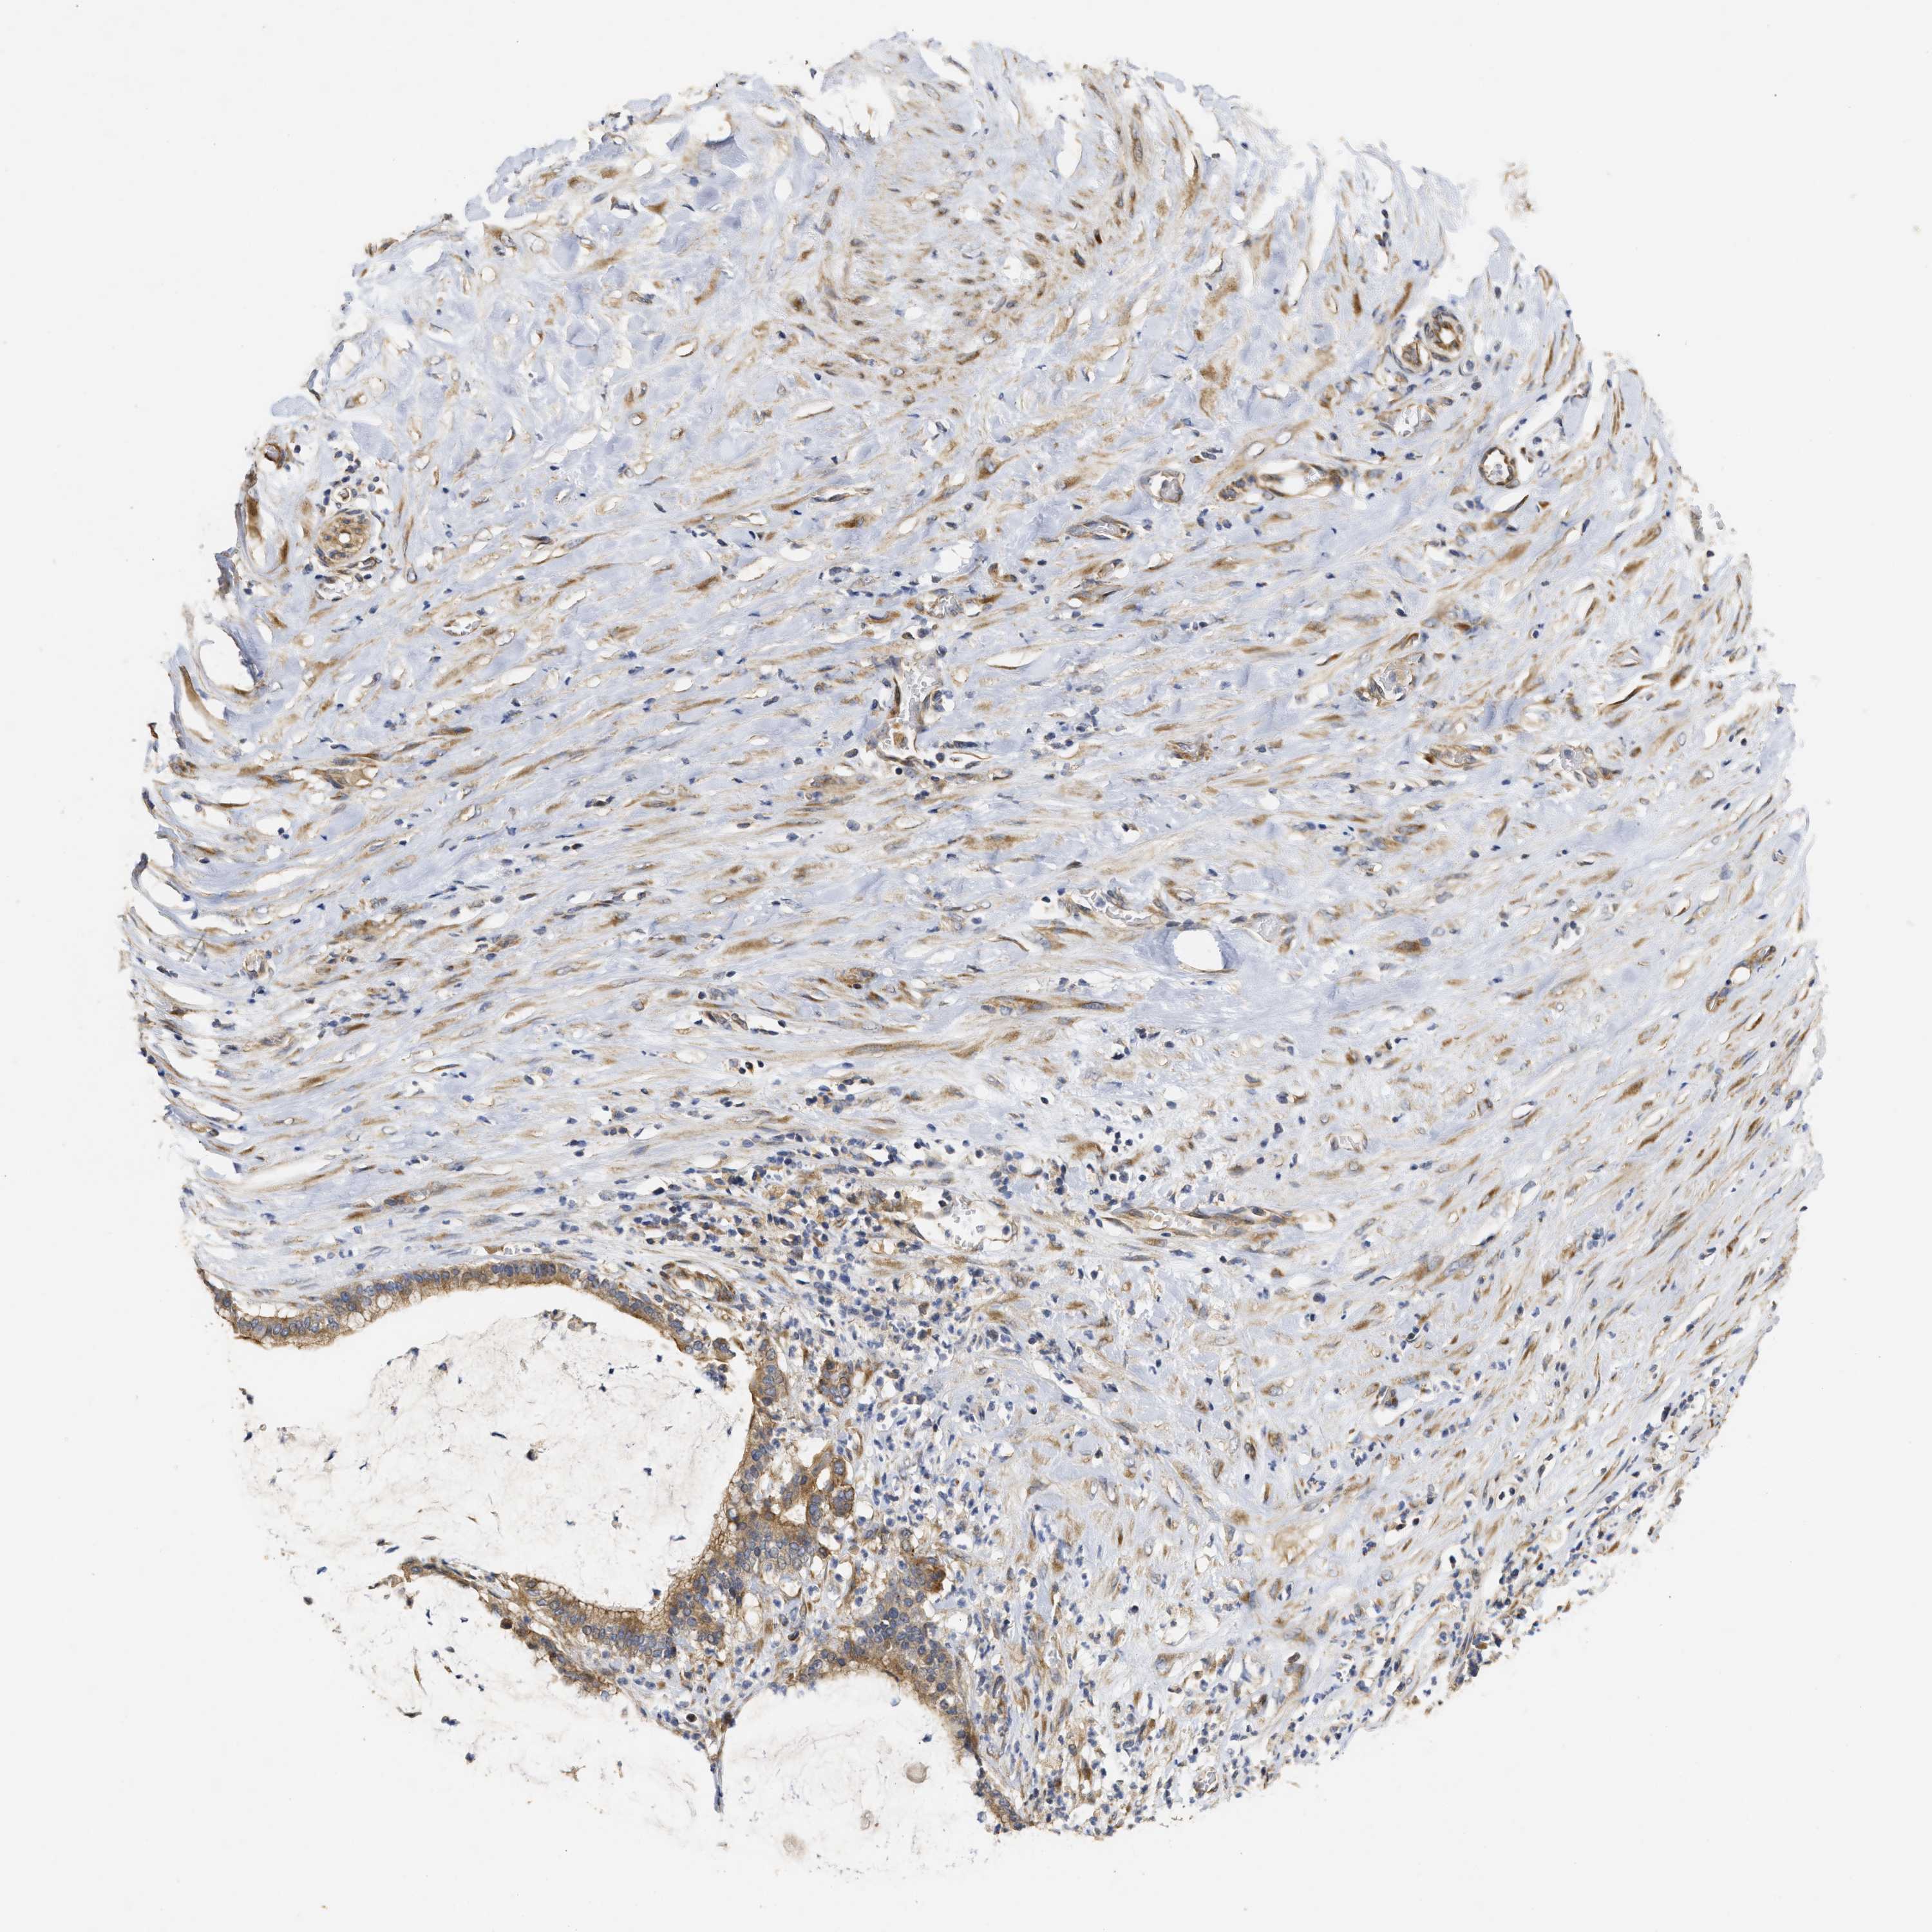

PANCREATIC CANCER - Protein expressioni

A mouse-over function shows sample information and annotation data. Click on an image to view it in a full screen mode. Samples can be filtered based on level of antibody staining by selecting one or several of the following categories: high, medium, low and not detected. The assay and annotation is described here.

Note that samples used for immunohistochemistry by the Human Protein Atlas do not correspond to samples in the TCGA dataset.

Antibody stainingi

Antibody staining in the annotated cell types in the current human tissue is reported as not detected, low, medium, or high, based on conventional immunohistochemistry profiling in selected tissues. This score is based on the combination of the staining intensity and fraction of stained cells.

Each image is clickable and will lead to virtual microscopy that enables deeper exploration of all samples and also displays staining intensity scores, fraction scores and subcellular localization as well as patient and tissue information for each sample.

Antibody HPA018127

Antibody HPA027887

Antibody CAB012302

Adenocarcinoma, NOS

Adenocarcinoma, metastatic, NOS